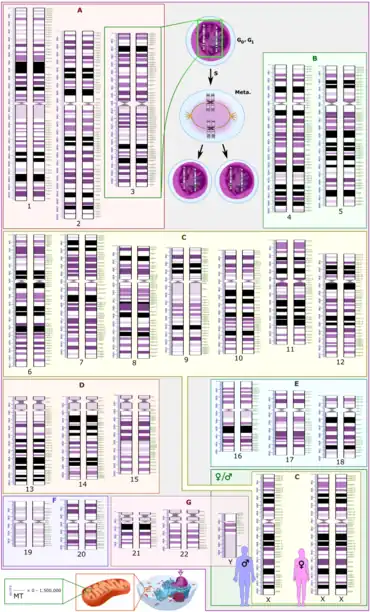

Polysomy is a condition found in many species, including fungi, plants, insects, and mammals, in which an organism has at least one more chromosome than normal, i.e., there may be three or more copies of the chromosome rather than the expected two copies.[1] Most eukaryotic species are diploid, meaning they have two sets of chromosomes, whereas prokaryotes are haploid, containing a single chromosome in each cell. Aneuploids possess chromosome numbers that are not exact multiples of the haploid number and polysomy is a type of aneuploidy.[2] A karyotype is the set of chromosomes in an organism and the suffix -somy is used to name aneuploid karyotypes. This is not to be confused with the suffix -ploidy, referring to the number of complete sets of chromosomes.

Polysomy is usually caused by non-disjunction (the failure of a pair of homologous chromosomes to separate) during meiosis, but may also be due to a translocation mutation (a chromosome abnormality caused by rearrangement of parts between nonhomologous chromosomes). Polysomy is found in many diseases, including Down syndrome in humans where affected individuals possess three copies (trisomy) of chromosome 21.[3]

Polysomic inheritance occurs during meiosis when chiasmata form between more than two homologous partners, producing multivalent chromosomes.[1] Autopolyploids may show polysomic inheritance of all the linkage groups, and their fertility may be reduced due to unbalanced chromosome numbers in the gametes.[1] In tetrasomic inheritance, four copies of a linkage group rather than two (tetrasomy) assort two-by-two.[1]

Types

Polysomy types are categorized based on the number of extra chromosomes in each set, noted as a diploid (2n) with an extra chromosome of various numbers. For example, a polysomy with three chromosomes is called a trisomy, a polysomy with four chromosomes is called tetrasomy, etc.:[4]

Germ line cells develop into eggs and sperm and the associated inherited material can be passed down to future generations.[32] As shown in the associated karyotype image, chromosomes 1–22 are grouped A-G. A population of male grasshoppers (Chorthippus binotatus) from the Sierra Nevada (Spain) are polysomic mosaics (coming from cells of two genetically different types) possessing an extra E group chromosome(chromosomes 16, 17 & 18) in their testicles.[33] Parents that exhibited polysomy did not pass the E chromosome abnormality to any of the offspring, so this is not something that is passed down to future generations.[33] Male grasshoppers (Atractomorpha similis) from Australia carry between one and ten extra copies of chromosome A9, with one being the most common in natural populations.[34] Most polysomic males produce normal sperm. However, polysomy can be transmissible through both the male and female parents through nondisjunction.[34]

Giemsa banding (G-banded karyotyping)

Karyotypes are commonly analyzed using Giemsa banding (G-banded karyotyping)). Each chromosome shows unique light and dark bands after they are denatured with trypsin and polysomies can be detected by counting the stained chromosomes. Several cells have to be analysed to detect mosaicism.[53]